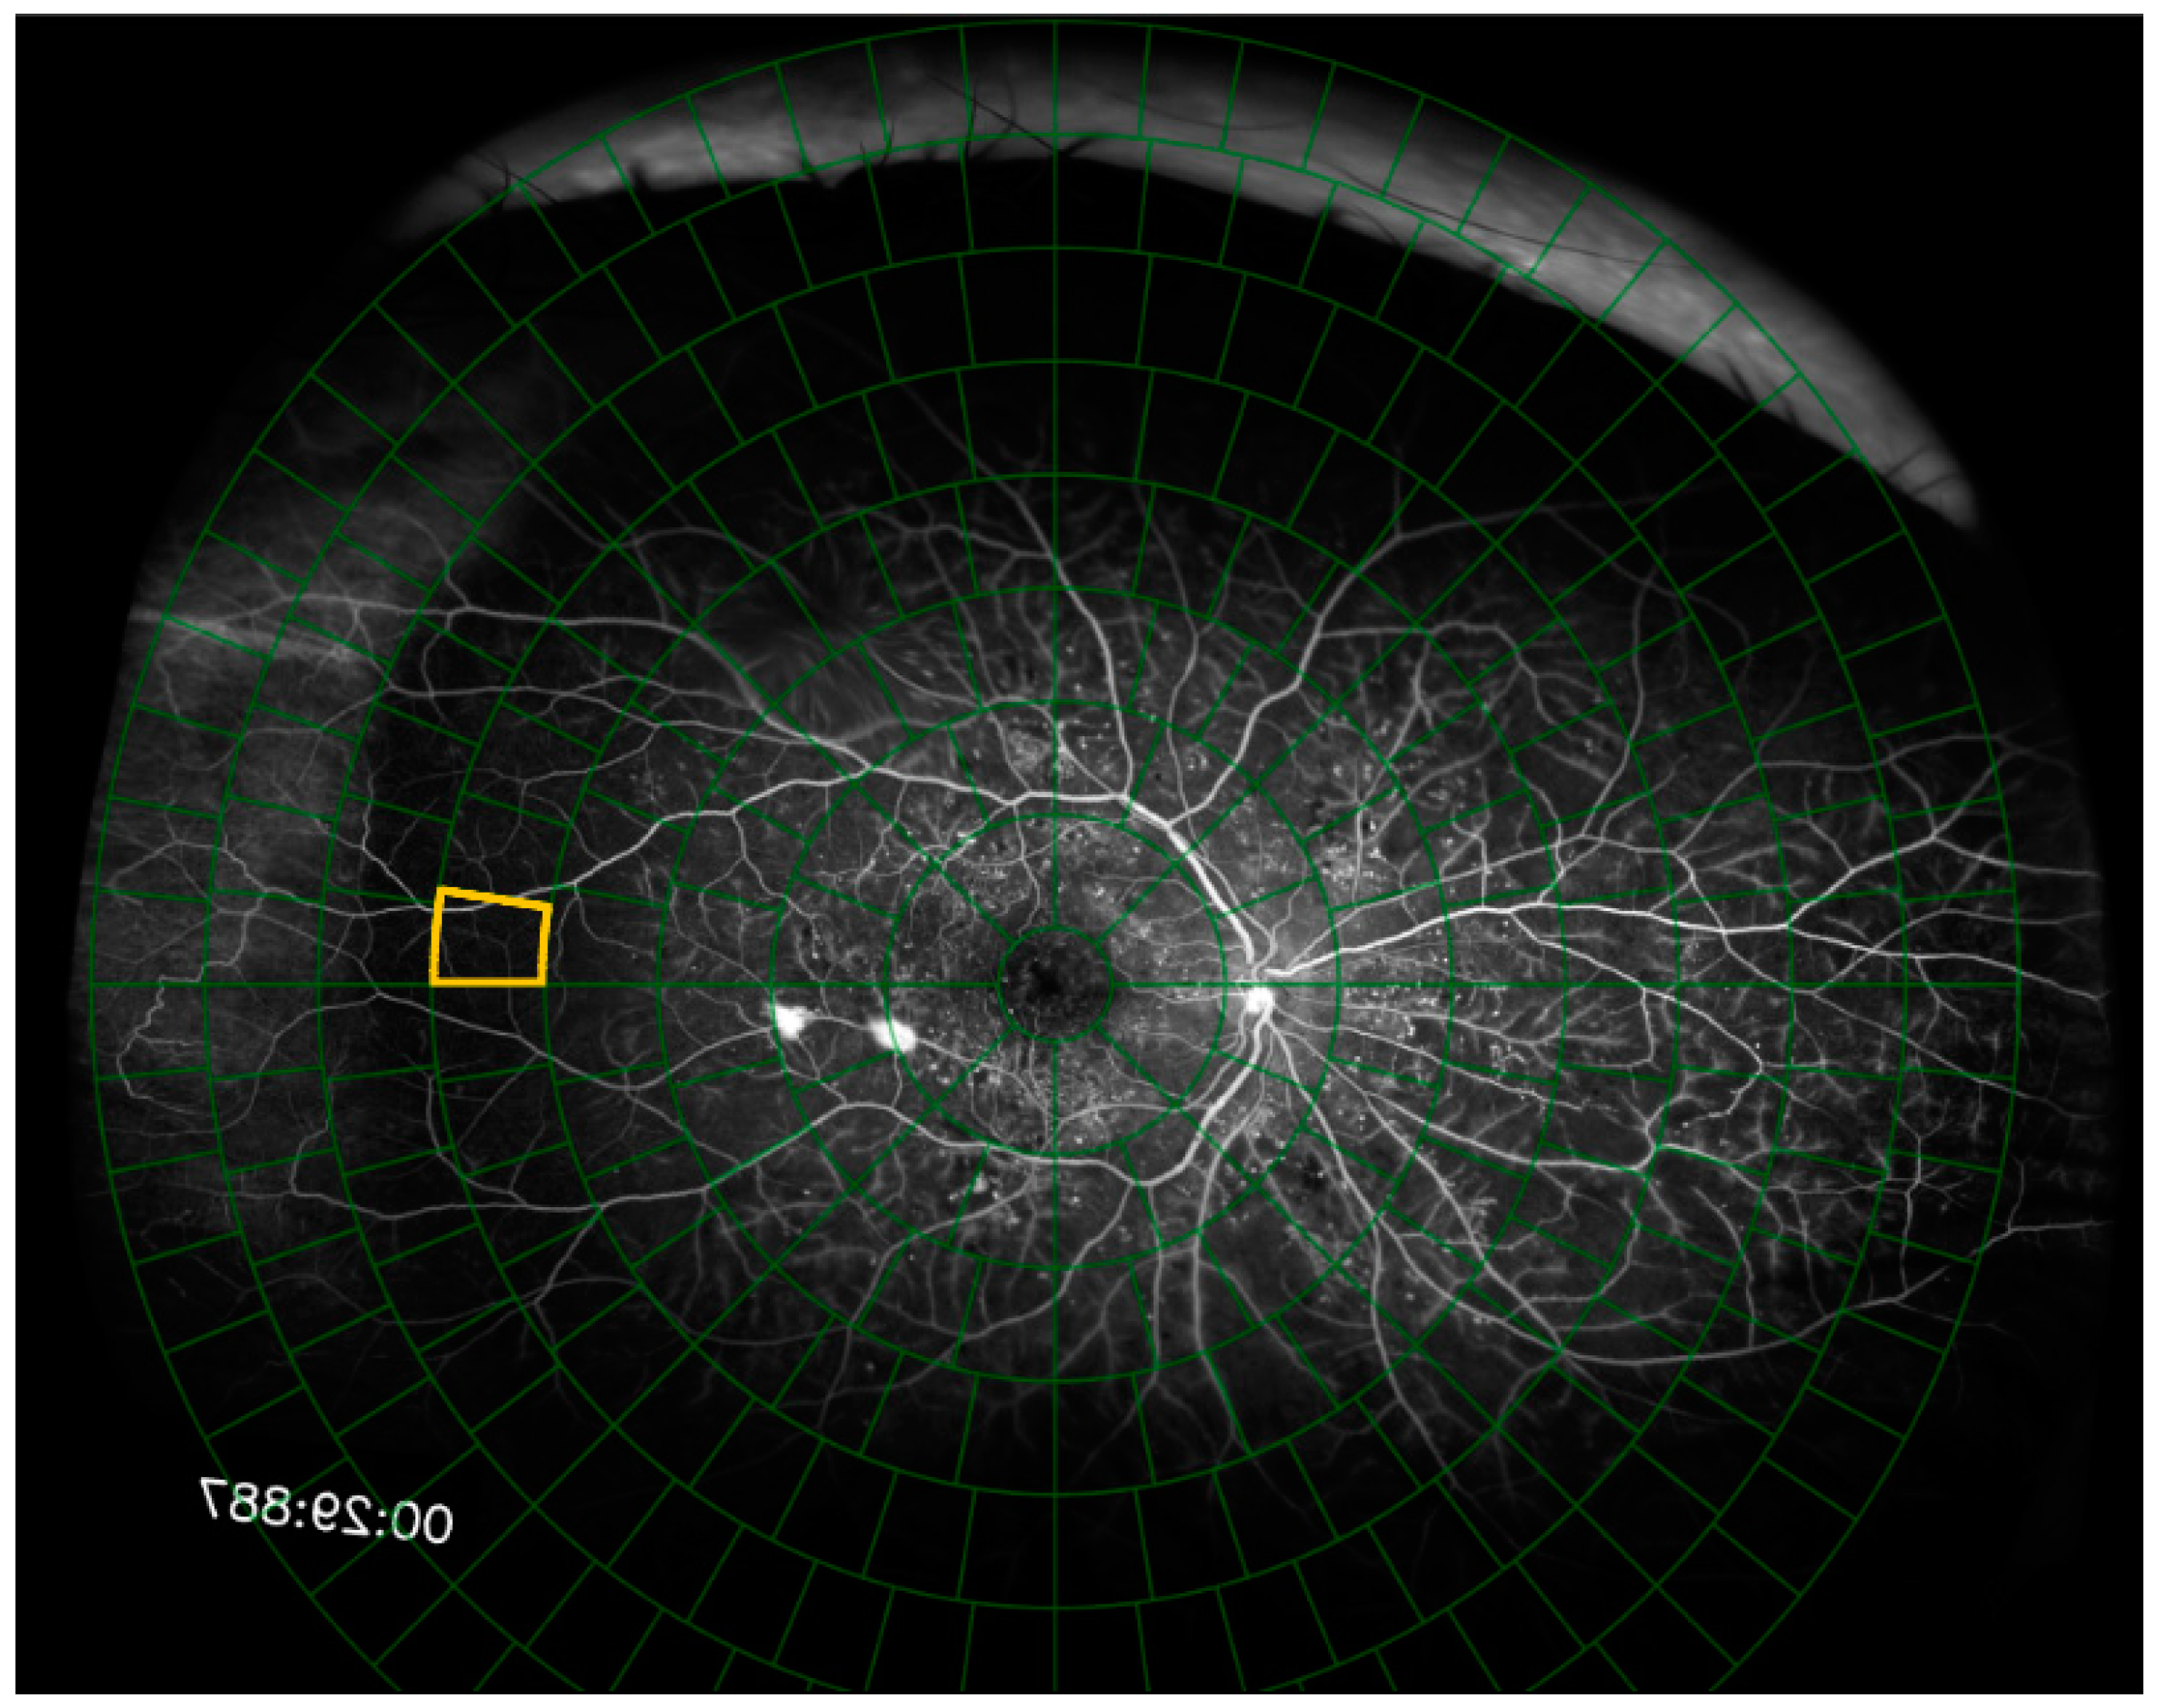

Figure 3. The fluorescein angiogram is presented to the user with the grid overlaid on the fluorescein angiogram. Image segments are presented to the user individually, and the currently selected image segment is outlined in yellow.

Each of the 50 fluorescein angiography images were uploaded to our online hypoperfusion grading software, created for the purposes of this study. For each image, the software prompted the user to identify and click on the fovea and the center of the optic disc. A grid of 289 cells arranged in 8 concentric rings around a central circular cell was overlaid on top of the image. The software shifted and rotated the image to center the fovea on the grid and align the fovea and the optic disc on the grid’s horizontal axis. The grid was scaled such that the distance between the fovea and the center of the optic disc spanned 9.5% of the grid’s diameter (Figure 2). The Python (Version 3, Python Software Foundation, Wilmington, DE, USA) code segments used to rotate, scale, and shift the fluorescein angiogram and grid are shown in Figure 3 and the full code is freely available online at https://github.com/OpenHealthSoftware/umich-isla-prototype/ (accessed on 10 March 2025). By assuming that the distance between the fovea and the optic disc was constant between eyes, the dimensions of the grid cells were determined such that each image segment contained an equivalent area of the fluorescein angiogram across different eyes (Figure 4). The distance between the fovea and the optic disc was measured to be 4.76 mm with a standard deviation of 0.34 mm in a previous study of 2836 individuals using fundus photography [17]. The method used to divide the disc into cells of equal area was described in 2012 by Benoit Beckers and Pierre Beckers [18]. The Michigan grid method involved the manual grading of each of these 289 cells but allowed for the localization of the grading of nonperfusion or hypoperfusion to a specific, defined spatial region for further segmentation of the image.